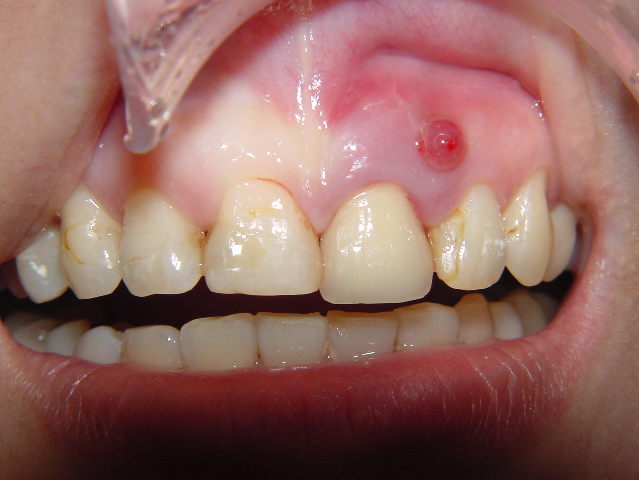

(1) 35歲女性,左上正中門牙牙根斷裂,在頰側有膿胞

(2)和患者討論補綴的幾種可能性;因鄰近的牙齒僅在頰側有表淺性的蛀牙,患者考慮以人工植牙修復;同時於術中做前牙的牙冠延長術,一方面可以達成更好的門牙長寬比例(美觀加分),同時也可以將取下的自體骨填補在原有的骨缺損;並預定將來於右上正中門牙製作瓷貼片,達成左右中門牙的對稱與美觀。